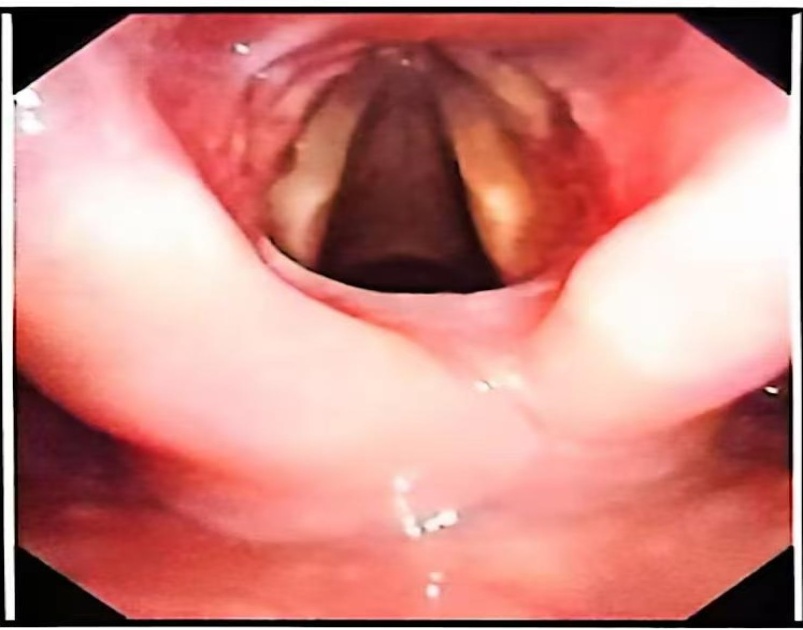

入院后完善血常规、血生化、凝血四项、术前九项、尿便常规、心电图、胸片等检查,电子喉镜下检查(见图1)会厌喉面双侧室带前中部可见一粉红色新生物。排除手术禁忌症后,2024年10月11日全麻前联合镜下喉功能重建术 + 喉噗黏连松解术,手术经过:1. 患者取仰卧位,气管插管静脉麻醉后常规消毒、铺巾;2. 经口导入前联合镜,见室带前中处与会厌喉面有1 × 1.5 cm大小粉红色新生物,局部白色瘢痕样组织增生,与周围组织分界清楚,表面平整,未见破溃、糜烂、出血及异常分泌物,术中切除新生物松解粘连室带,喉剪修剪新生物边缘,电凝新生物基底止血,检查无组织残留,取新生物病损送病检;4. 术毕,安返,术中出血约5 ml。术后激素抗炎、消肿,止血,雾化吸入对症治疗。术后病理检查(图2)示:(喉部病损)送检组织衬覆少许鳞状上皮,固有层充血、出血及水肿,伴梭形细胞及胶原纤维增生,淋巴细胞、浆细胞和少许中性粒细胞浸润,考虑瘤样纤维组织增生。免疫组化结果回报:SOX-10 (−),β-catenin (−),SMA (+),Ki67 (个别细胞+),MSA (−),Desmin (−),CD34 (血管+),MyoD1 (−),myogenin (−),STAT6 (−),Vimentin (+),ALK (−)。特殊染色结果:弹力纤维(−)。术后予以消肿、禁声、止血等对症治疗,术后我们进行了随访,在随访复查中,患者恢复良好,术后复查电子喉镜(图3)示:喉蹼术后改变,声带活动好,闭合可。患者声嘶改善,呼吸较术前顺畅,无咽痛、咽痒、吞咽困难、咳痰、痰中带血等不适,康复出院。

Figure 1. Electronic laryngoscopy shows: A pink neoplasm is visible in the anterior middle part of the bilateral ventricular bands on the laryngeal surface of the epiglottis

1. 电子喉镜示:会厌喉面双侧室带前中部可见一粉红色新生物